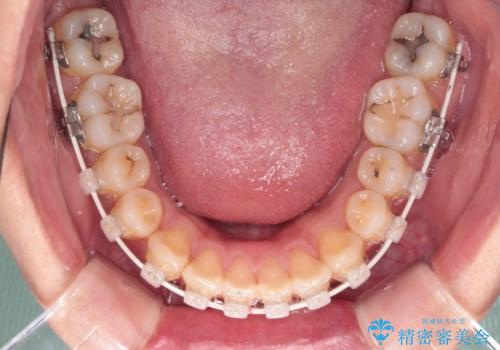

深い咬み合わせと前歯の隙間 ハーフリンガルによる矯正治療

- 矯正装置

- ハーフリンガル

- 咬み合わせにより上顎正中に隙間ができているとのことで来院された患者様です。

インビザラインは自己管理が煩わしく、表側のワイヤー装置は目立つので避けたいとのことで、上顎だけが裏側装置のハーフリンガルにて矯正治療を行うこととしました。